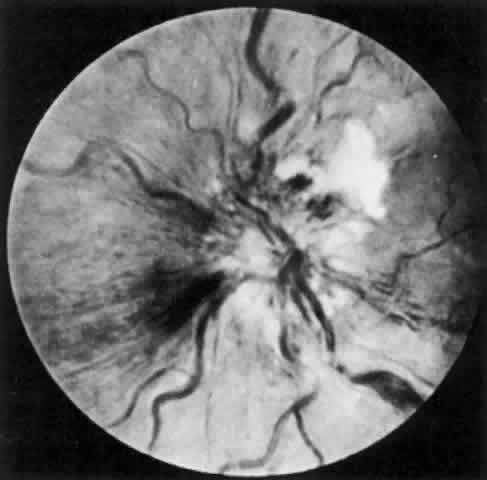

Lens-induced uveitis, Behçet's disease, and the occlusive vasculitis of the ganglion cell layer of the retina produced by lupus erythematosus may all be immune-complex-mediated reactions (Fig. 7). Both homologous and heterologous retinal extracts have been used to produce experimental endophthalmitis in animals, and immunization with these extracts (antigens) produces both antibody and T-cell responses.59 Eales disease may also be an immune-complex disease produced by antibody-dependent lymphocytes.60

Fig. 7. A patient with systemic lupus erythematosus showing an occlusive vasculitis in the retina.